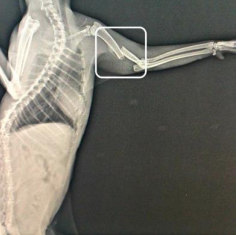

HUMERUS KIRIĞINA MÜDAHALE – KEDİ